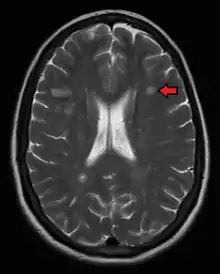

MRI brain scan produced using a Gradient-echo phase sequence showing an iron deposit in a white matter lesion (inside green box in the middle of the image; enhanced and marked by red arrow top-left corner)[213]

Improvement in neuroimaging techniques such as positron emission tomography (PET) or MRI carry a promise for better diagnosis and prognosis predictions. Regarding MRI, there are several techniques that have already shown some usefulness in research settings and could be introduced into clinical practice, such as double-inversion recovery sequences, magnetization transfer, diffusion tensor, and functional magnetic resonance imaging.[216] These techniques are more specific for the disease than existing ones, but still lack some standardization of acquisition protocols and the creation of normative values.[216] This is particularly the case for proton magnetic resonance spectroscopy, for which a number of methodological variations observed in the literature may underlie continued inconsistencies in central nervous system metabolic abnormalities, particularly in N-acetyl aspartate, myoinositol, choline, glutamate, GABA, and GSH, observed for multiple sclerosis and its subtypes.[217] There are other techniques under development that include contrast agents capable of measuring levels of peripheral macrophages, inflammation, or neuronal dysfunction,[216] and techniques that measure iron deposition that could serve to determine the role of this feature in MS, or that of cerebral perfusion.[216]